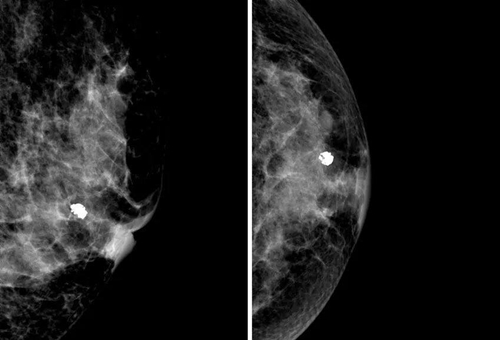

乳房的鈣化點(diǎn)大部分都是良性的,或伴有其他良性病變,如乳腺增生。所以,乳房鉬靶上如果看到大大的白點(diǎn),通常就是良性鈣化點(diǎn),如纖維腺瘤就常常會在鉬靶的影像上出現(xiàn)爆米花狀的粗糙大白點(diǎn)。

2. 女性乳房里常常有纖維腺瘤,腺瘤里的腺體也會聚積鈣鹽,在影像上呈現(xiàn)出粗大的白點(diǎn);